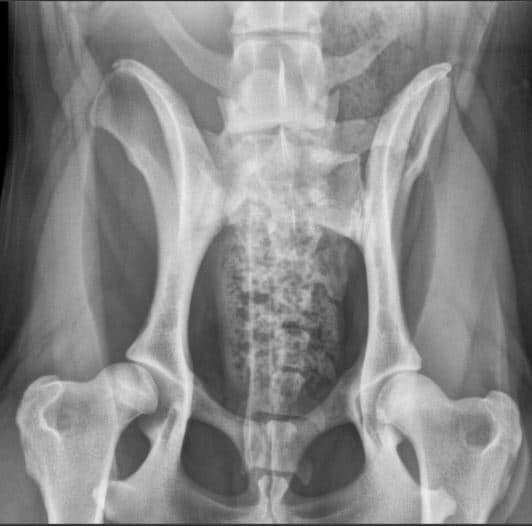

LTV2; symmetrinen

LTV3; epäsymmetrinen; oikeanpuoleisessa VD-kuvassa S1 on vasemmalla puolella ristinikaman ja oikella puolella lannenikaman kaltainen okahaarakkeen kera.

LTV3, epäsymmetrinen lanne-ristinikama näyttää olevan muita muotoja harmillisempi. Joissain tapauksissa epäsymmetriseen lanne-ristinikamaan liittyy vino lantio, joka saattaa aiheuttaa myös lonkkien epätasaista kehitystä. Tämä on varsin loogista; kun lantio on vino kohdistuu paine lonkkamaljoille epätasaisesti. Pidemmän ajan kuluessa epätasapaino voi kuluttaa toista lonkkamaljaa nopeammin ja aiheuttaa tätä kautta nivelrikkoa.

KoiraNetin mukaan 38,9% LTV3-lausunnon saaneista rhodesiankoirista on saanut lonkkien osalta lausunnon, jossa toinen lonkka on 1-2 astetta toista huonompi, esimerkiksi A/C (lokakuu 2020). Tutkimustulos LTV3 ei kerro koiran lantion asentoa.